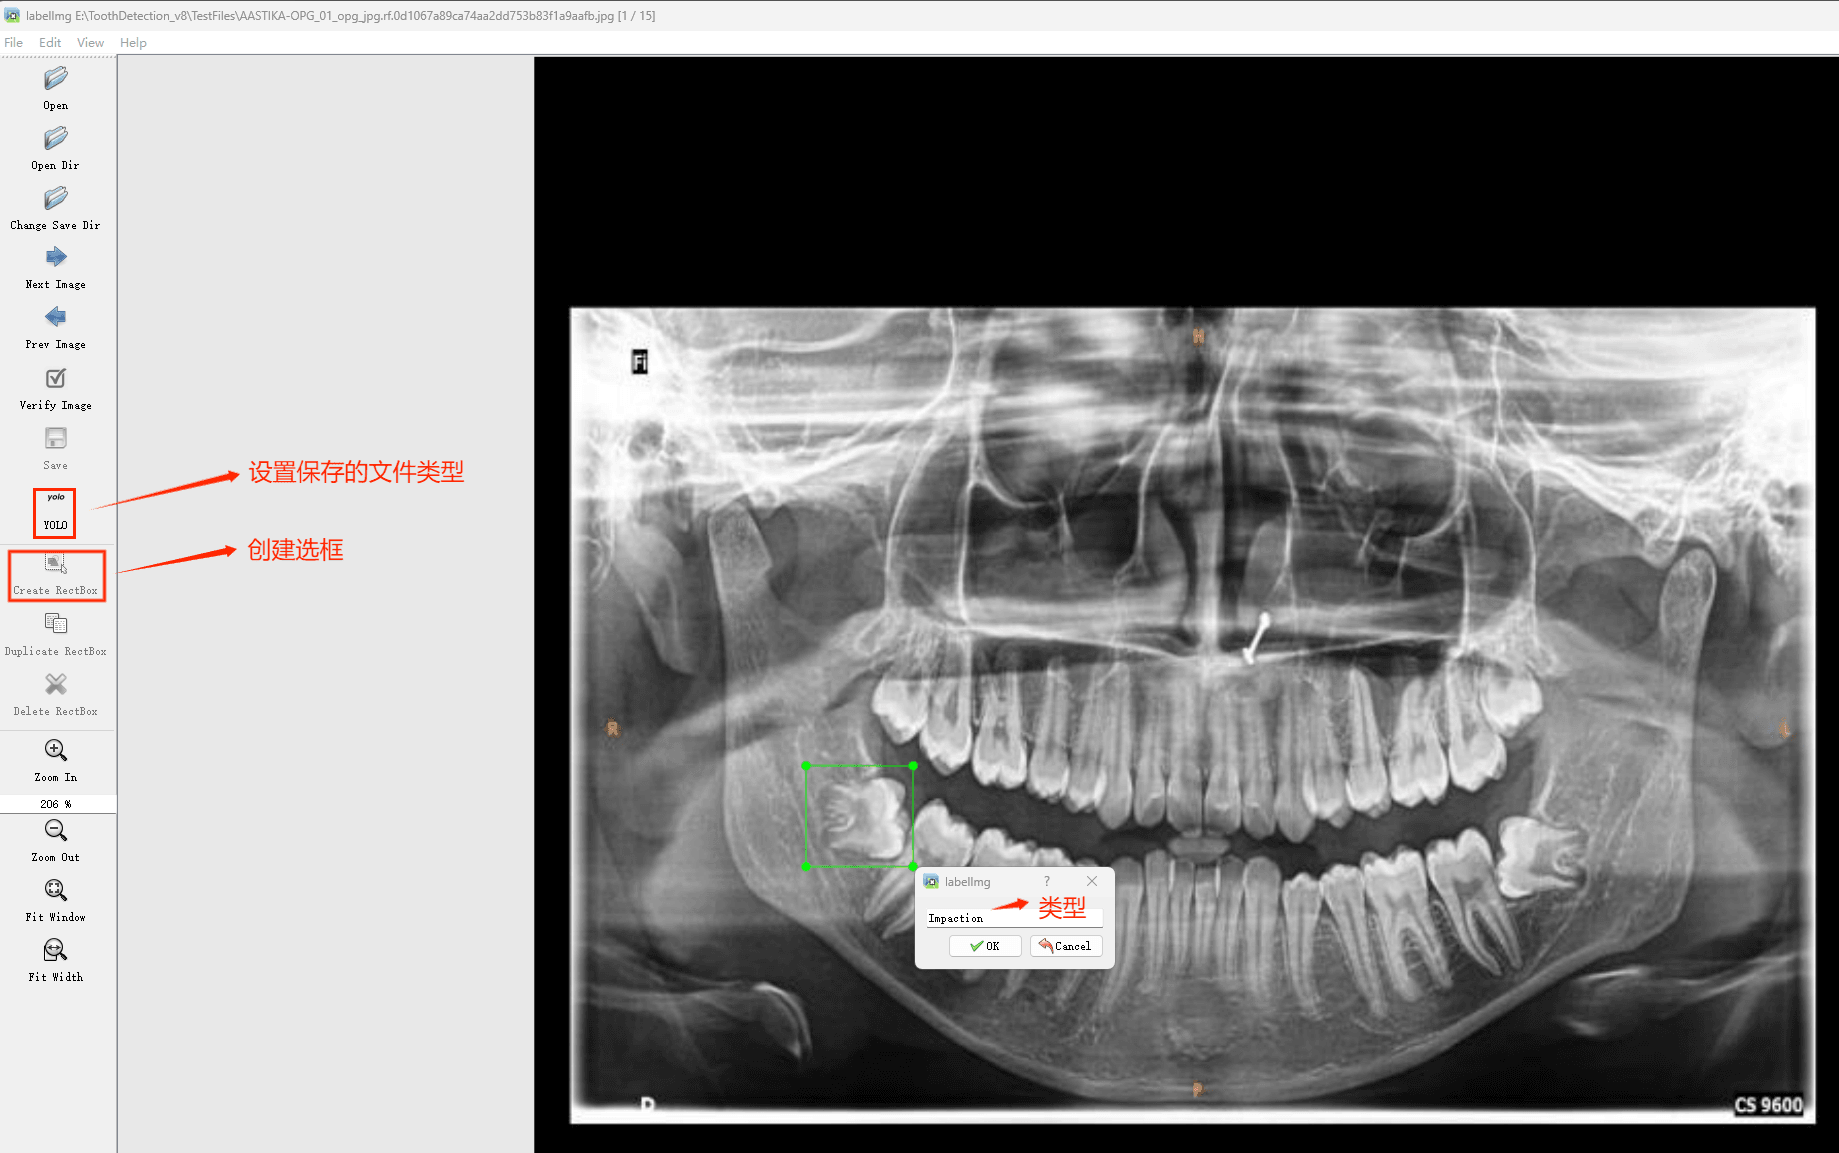

(4)YOLO模式创建标签的样式

存放标签信息的文件的文件名为与图片名相同,内容由N行5列数据组成。

每一行代表标注的一个目标,通常包括五个数据,从左到右依次为:类别id、x_center、y_center、width、height。

其中:

–x类别id代表标注目标的类别;

–x_center和y_center代表标注框的相对中心坐标;

–xwidth和height代表标注框的相对宽和高。

注意:这里的中心点坐标、宽和高都是相对数据!!!

存放标签类别的文件的文件名为classes.txt (固定不变),用于存放创建的标签类别。

完成后可进行后续的yolo训练方面的操作。